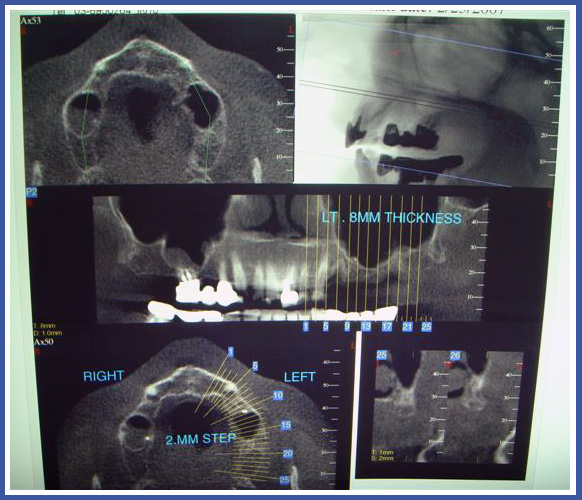

6.צילום סי.טי (COMPUTERIZED TOMOGRAPHY)

צילום שנעשה במכון רנטגן. בצילום זה יש שימוש משולב בין קרני הרנטגן וסורק ממוחשב אשר באמצעות חישובים מורכבים מסוגל לקבוע באילו רקמות וכיצד תספג הקרינה.

ברפואת שיניים משתמשים בדרך כלל ב CT רגיל שמייצר "פרוסות" של הלסתות והשיניים ומאפשר לרופא לראות את האנטומיה המדוייקת של העצם , השיניים, הסינוס המקסילרי ותעלת העצב .

בדרך כלל צילומי CT נעשים בנוסף לצילום הפנורמי ולפני השתלות שיניים לצורך קביעת מיקום מדויק של השתל.

כמו כן, צילומים אלו מסייעים באיתור תהליכים דלקתיים וגידולים.